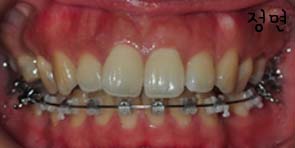

먼저 현재상태를 전반적으로 볼까요??

킬본교정기를 달고 난후 첫 월치료라 두근거리는마음과 함꼐 치과로 고고싱!!

사진과 같이 보시면 입천장에 스크류가 심어졌을때의 모습이 보이시나요? 사진과 같이 두개의 스큐르를 심은후 고무로된 연결고리로 연결하여 킬본교정장치에 걸어서 당기고 당기고~ 를 해주는겁니다 *,*

하악 와이어를 교체하고 와이어를 자르고 한쪽 끝이 약간 입안에서 닿으면서 거친 느낌이 아주 살짝 나는 것을 말씀들이니 좀더 부드럽게 잘라낸후 살짝 갈아주셨어요 그러니 훨씬 느낌이 부드럽게 마무리 되었어요 와이어를 자르는것말고도 갈아서 마무리도 해주시니 더욱 세심하게 마무리를 해주신것에 감사한 마음입니다. ㅎㅎㅎ